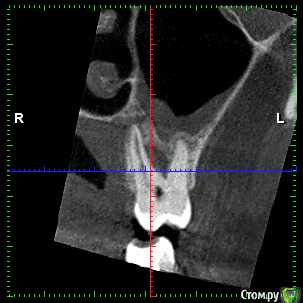

rezo47 Опубликовано 24 сентября, 2015 Автор Поделиться Опубликовано 24 сентября, 2015 Только пришло КТ, вопросов стало больше((( Ссылка на комментарий

kriokov Опубликовано 24 сентября, 2015 Поделиться Опубликовано 24 сентября, 2015 27 удаляйте Ссылка на комментарий

rezo47 Опубликовано 24 сентября, 2015 Автор Поделиться Опубликовано 24 сентября, 2015 (изменено) 27 удаляйтеДиагноз? Изменено 24 сентября, 2015 пользователем rezo47 Ссылка на комментарий

kladoffka Опубликовано 24 сентября, 2015 Поделиться Опубликовано 24 сентября, 2015 Хр пр 2 Ссылка на комментарий

kriokov Опубликовано 24 сентября, 2015 Поделиться Опубликовано 24 сентября, 2015 Диагноз?что хотите, на выбор(например- "не жилец" ) Ссылка на комментарий

red_butler Опубликовано 24 сентября, 2015 Поделиться Опубликовано 24 сентября, 2015 сначала гистология, потом лечение Ссылка на комментарий